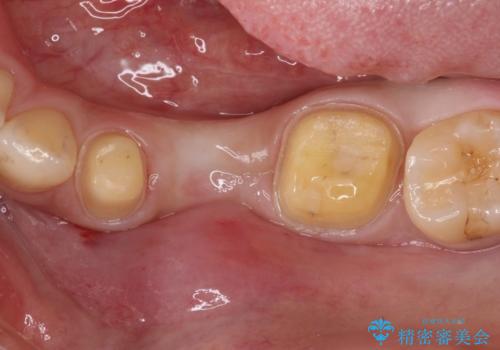

奥歯が痛い。乳歯を抜歯し、ブリッジによる咬合回復。

- 晩期残存した乳歯が痛くなったことを主訴に来院されました。

歯周病が進行していたため、抜歯を行い咬合回復を行いました。

インプラントは希望されなかったため、ブリッジにて治療を行っております。